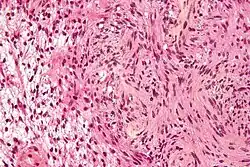

The so-called acoustic neuroma of NF2 is in fact a schwannoma of the nervus vestibularis, or vestibular schwannoma. The misnomer of acoustic neuroma is still often used. The vestibular schwannomas grow slowly at the inner entrance of the internal auditory meatus (meatus acousticus internus). They derive from the nerve sheaths of the upper part of the nervus vestibularis in the region between the central and peripheral myelin (Obersteiner-Redlich-Zone) within the area of the porus acousticus, 1 cm from the brainstem.